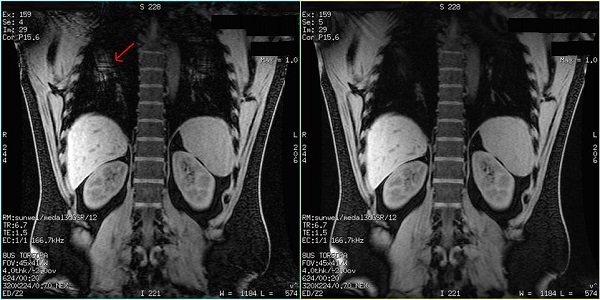

Figure 5. Example of: Coronal reformat of axial LAVA-Flex scan with ARC Phase = 2 (A/P). Coil position is well matched with scan coverage in Accelerated A/P direction